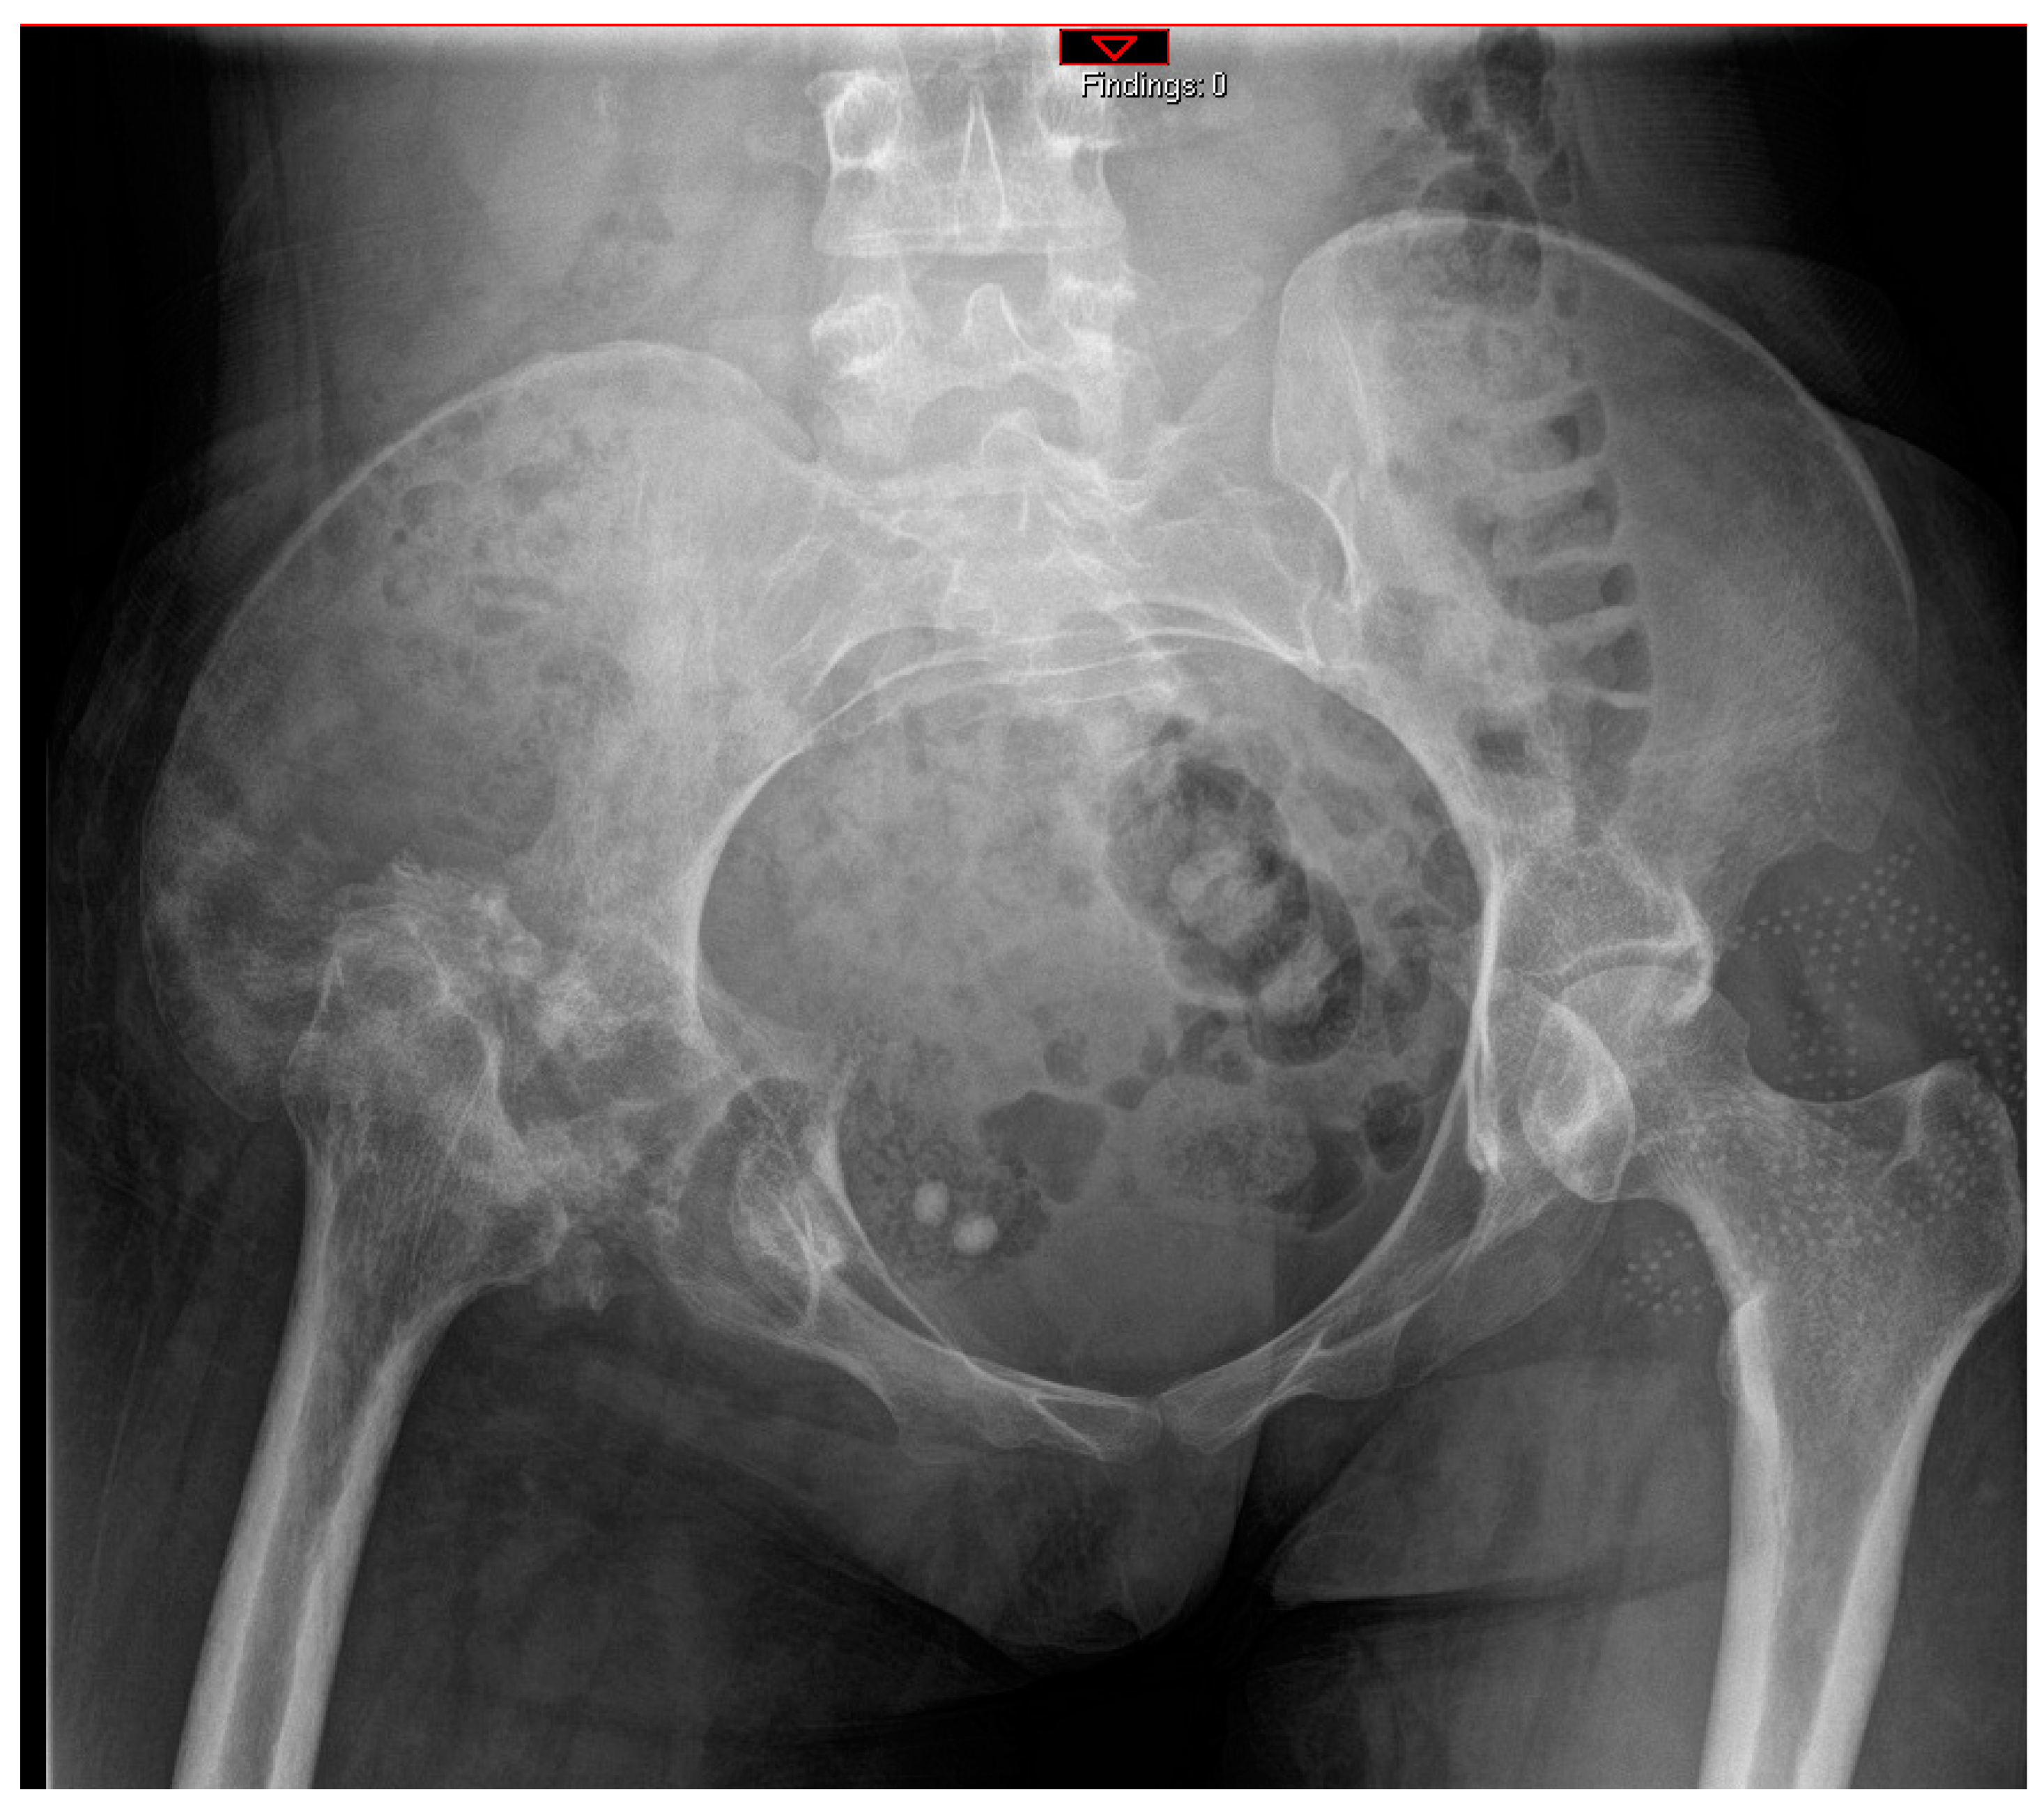

5.1. Surgical Technique